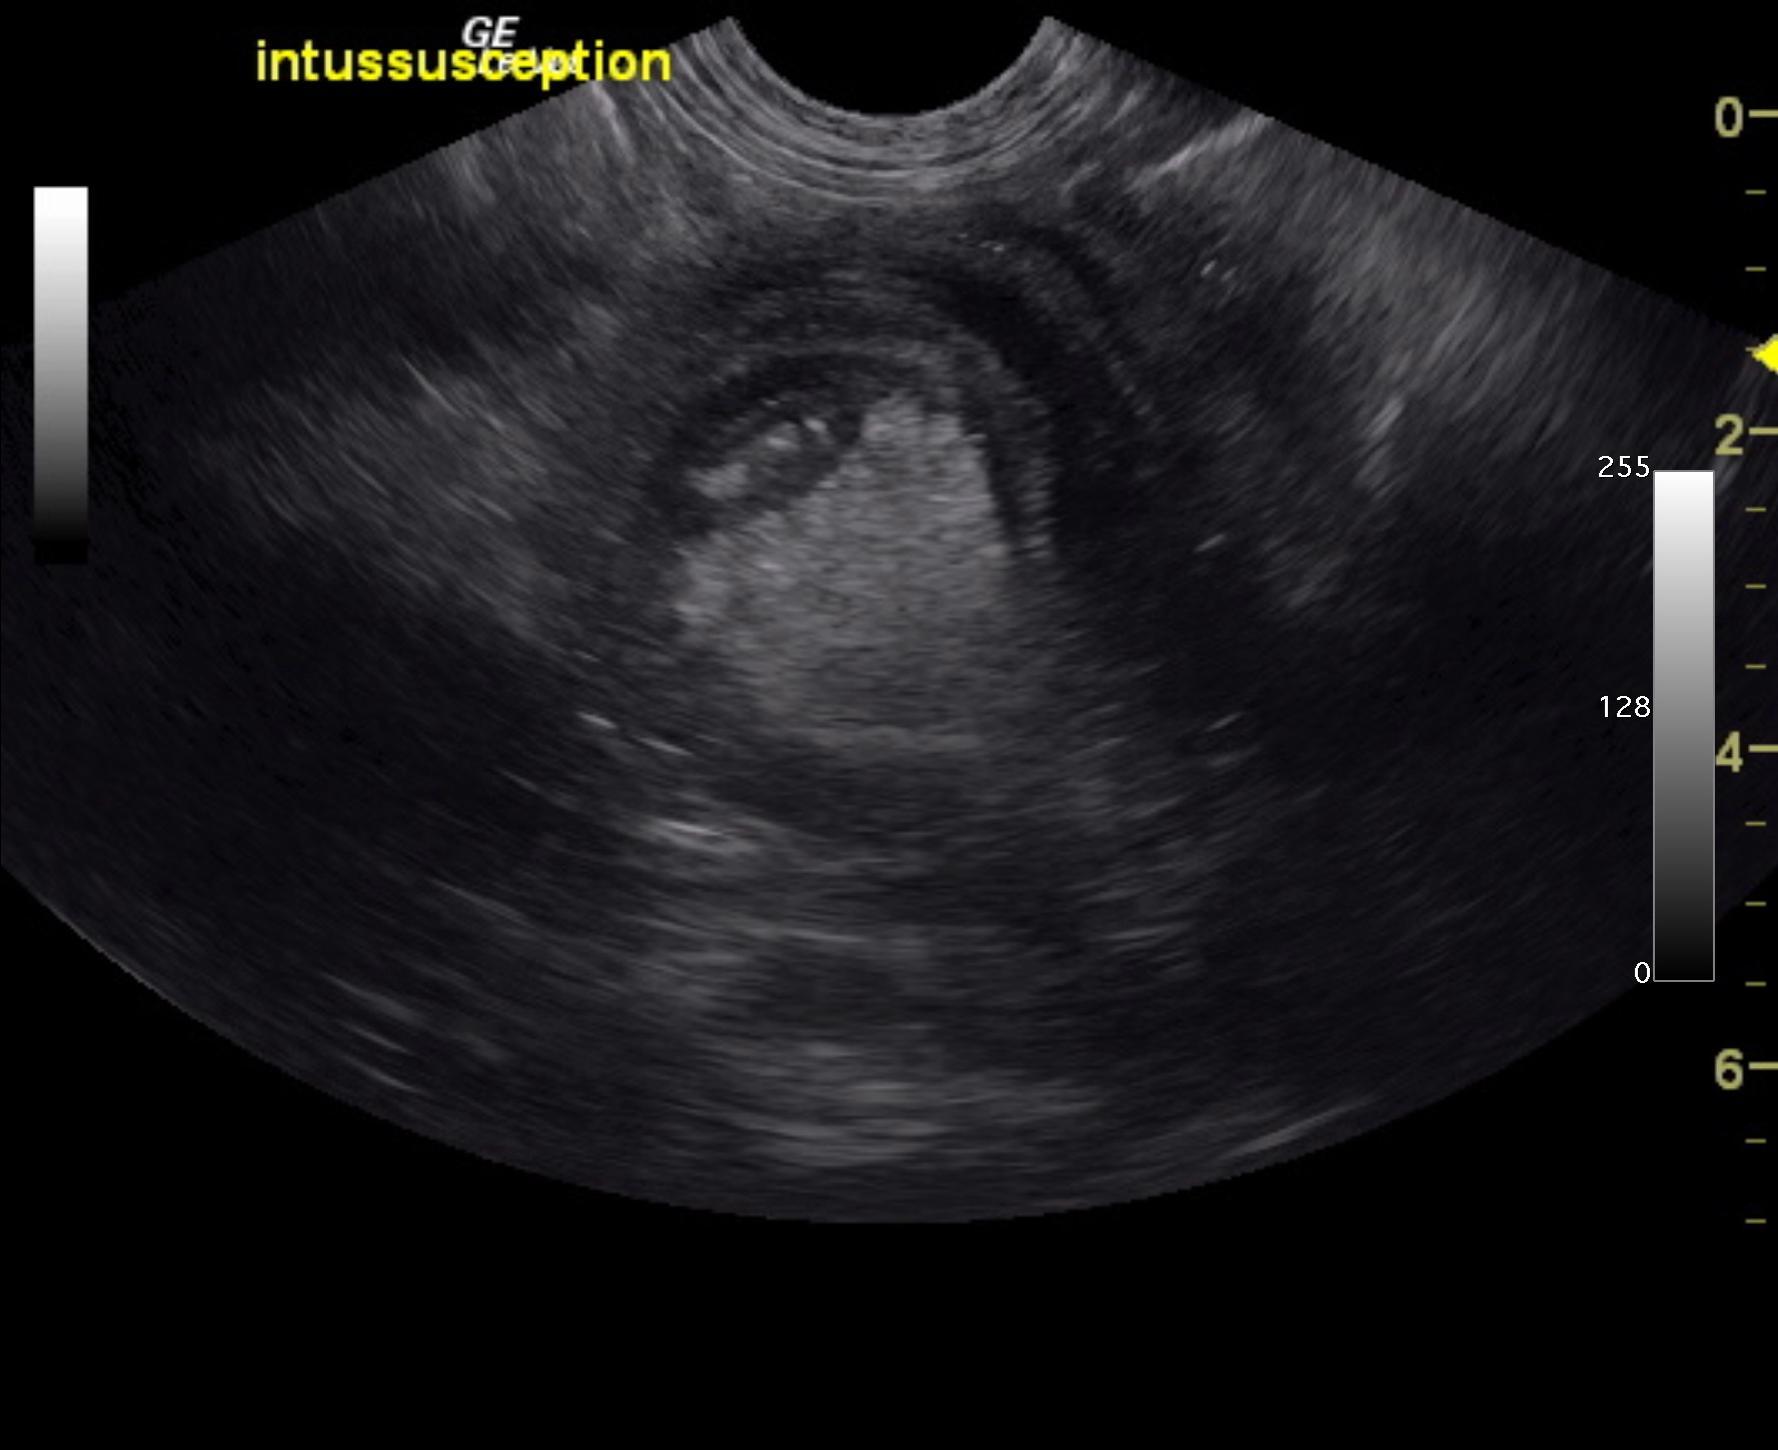

A 6-month-old intact male Labrador was presented for evaluation of diarrhea and vomiting for approximately 1 week and more recently only hemorrhagic diarrhea.

A 6-month-old intact male Labrador was presented for evaluation of diarrhea and vomiting for approximately 1 week and more recently only hemorrhagic diarrhea.